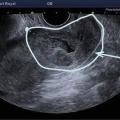

L’échographie, indispensable, doit examiner le pelvis mais aussi l’abdomen. Elle est donc réalisée par voie endovaginale, sus-pubienne et abdominale. On peut visualiser une masse latéro-utérine (fig. 1). Au sein de cet hématosalpinx, un sac gestationnel peut être visible, voire un embryon (fig. 2) ayant parfois une activité cardiaque positive. Le passage de la sonde à ce niveau est douloureux.

Souvent, le principal signe est indirect :

– vacuité utérine (fig. 3) et taux de hCG supérieur à 1 500 UI/L, fortement évocateurs. En cas de métrorragies, une lame d’hématométrie peut être visible en intra-utérin (« pseudo-sac gestationnel » : image hypo-échogène centrée dans la cavité, sans couronne trophoblastique) ;

Remerciements au Dr Gilles Grange, maternité Port-Royal, Paris pour les figures 1, 2 et 3.